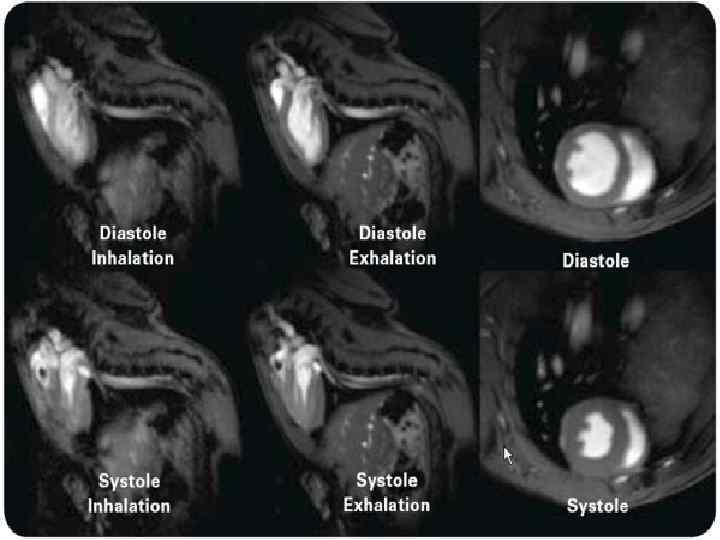

МАГНИТНО-РЕЗОНАНСНАЯ ТОМОГРАФИЯ(МРТ) СЕРДЦА Магниттi - резонанстық томография орталық жүйке жүйесi, омыртқаның ауруларын диагностика арқылы зерттеудiң аналог болмайтын сирек кездесетiн iс жүзiнде бұлшық еттiк болып табылады - буын жүйе және iшкi органдардың қатары. Сутектiң протондарын адамның организмінде резонанста негiзделгеннiң зерттеу онының магниттi алаңына үй-жайда. Сәулелiк жүктеменiң жоқтығы емделушi үшiн магниттi - резонанстық томография қауiпсiз iстейдi және бiрнеше тексерулер қатар өткiзуге мүмкiндiк бередi

Жағдайларды қатарда көк тамырiшiлiк қарама-қарсы күшейтуi бар зерттеудiң өткiзу МРТ диагностикалық қажеттiлiгi пайда болады. Зерттеудiң мәлiметтерi дәрiгер МРТ емдеушi дәрiгер немесе бағыт бойымен тек қана жүргiзiледi. Қарама-қарсы препараттың енгiзуi қосымша реакциялардың ең төменгi тәуекелiнде болады. Сiзгеге контрасты заттың енгiзуi жағдайда сауалнаманы толтыруға ұсыныс жасайды - қарама-қарсы препараттың көктамырiшiлiк енгiзуiне ақпараттық келiсiмнiң парағы.

Зерттеуге абсолюттiк қарсы көрсетулермен жатады: ми ыдыстарында кардиостимулятордың бар болуы, ферромагниттi имплантовтары, клипс. Зерттеу бұл жағдайдалардағы қатал қарсы көрсеткен. (зерттеу өткiр қажеттiлiктiң жанында жүргiзiле алады) салыстырмалы қарсы көрсетулерге металлдың мазмұнымен жүктiлiктiң бiрiншi триместрi, жүректiң жасанды клапандары, орнын толтырмалған жүрек мүкiсi, инсулин сорғылары, импланты, металлдық брекетыларда әкетедi. Сонымен бiрге темiрi бар бояуларды қолданумен салыстырмалы қарсы көрсетулер сияқты қарау керек болуға iстеп шығылған татуировкалар.